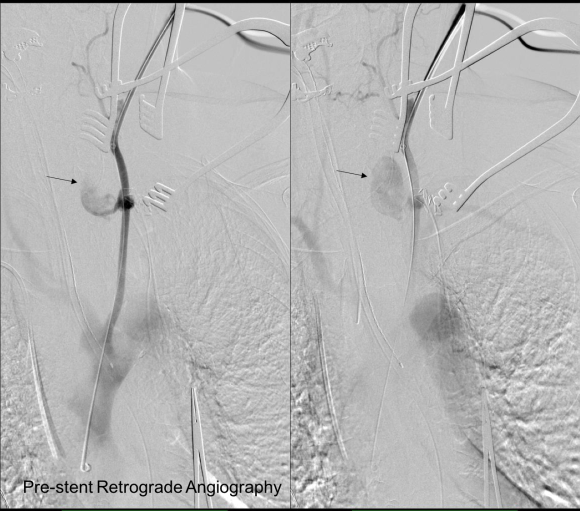

As seen below, the graft excluded the celiac and SMA. Late in the phase of the final aortogram (second panel) there was an endoleak that persisteed despite multiple ballooning. The timing suggested the intercostals and phrenic vessels contributed to a type II endoleak, but it was concerning.

This worked to relieve the kink as evidenced on the aortogram above. After closing the laparotomy, I placed a chest tube in the right chest. The patient had a course prolonged by a classic systemic inflammatory response syndrome, with fevers, chills, and leukocytosis. He bled for a while but stopped with correction of his coagulopathy. All blood cultures were negative, but a CT scan was performed out of concern for the endoleak, and the possibility of continued bleeding.